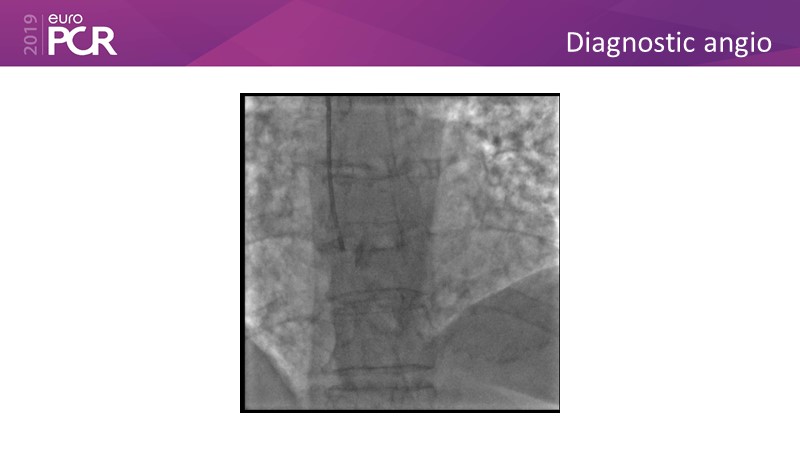

Distal left main stenosis: how to treat optimally with dedicated bifurcation stent BiOSS Lim C. Case-based session

Consult this session to learn more about the multiple technological options with dedicated bifurcation stent for complex left main bifurcation lesions, and the applicability of this stent for the different clinical presentations.